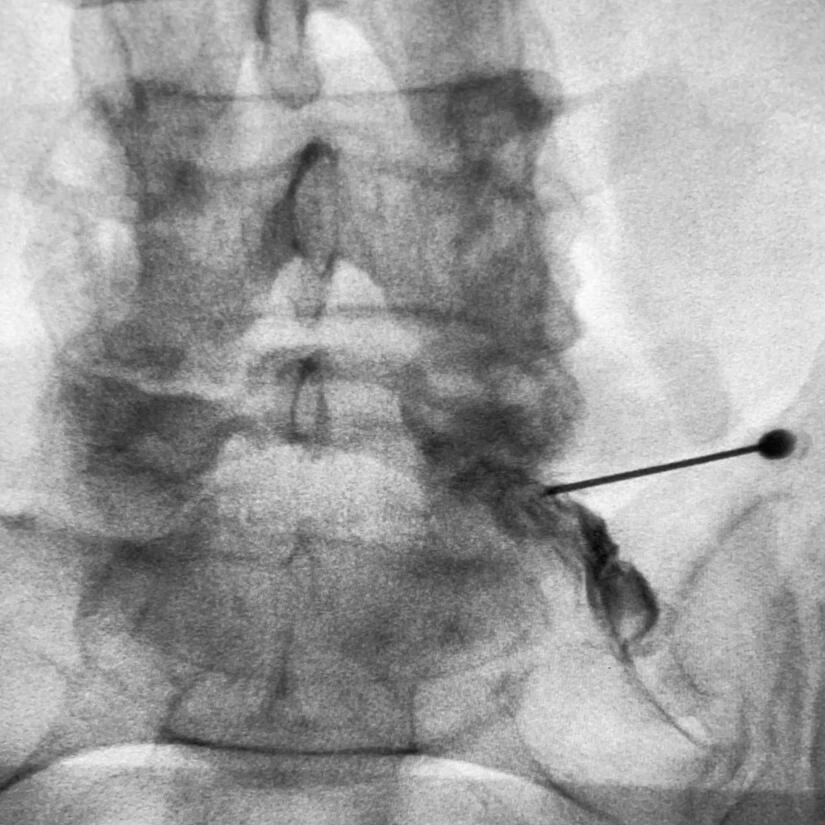

Transforaminal epidural nerve root injection